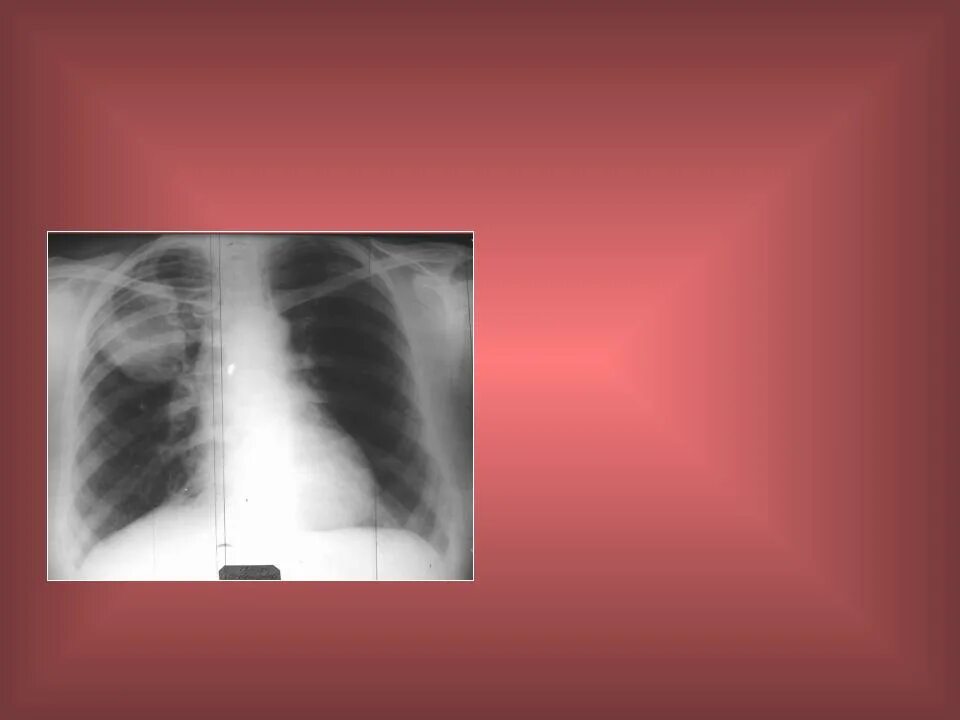

Диагноз сегмент